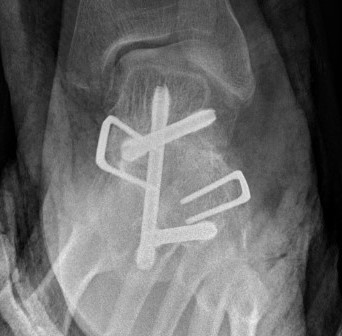

Open Calcaneo-navicular bar resection

Technique

Anterolateral / Ollier approach

- 1cm distal to fibular tip obliquely across sinus tarsi to superolateral margin TNJ

- protect superficial CPN

- EDL & P tertius anteriorly

- peroneals plantarward

- elevate EDB proximal to distal

- beware of its motor branch from DPN

- expose sinus tarsi / anterior process calcaneum and bar

Resection

- resect 1cm of bone with osteotomes

- check with on table oblique intra-operative image

- interpose fat / EDB / bone wax into defect